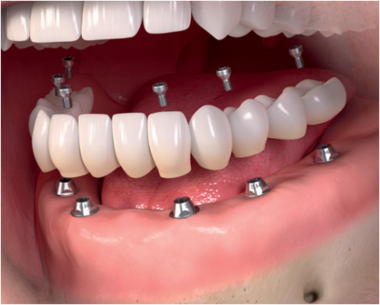

Звичайно ж, найкращим є протезування за принципом «один імплант – одна коронка», коли на імплант встановлюється «індивідуальна» коронка, однак такий варіант досить дорогий і зазвичай використовується при відсутності декількох зубів. При відсутності значного числа зубів замінювати їх всі імплантами недоцільно з фінансової точки зору, так як коштувати це буде недешево, більш раціональним буде установка на імпланта мостовидного протеза, коли, наприклад, 2 імпланта стануть опорою для 3-4 штучних зубів. Хоча, звичайно ж, при бажанні пацієнта замінити всі відсутні зуби штучними, це цілком здійсненно – можуть бути встановлені навіть 14 штучних коренів («зуби мудрості» не відновлюються, так як вони не мають особливого функціонального значення).

Які протези можуть бути встановлені на імплантатах? Та які завгодно – незнімні, знімні, умовно-знімні, комбіновані. Незнімні протези можуть бути закріплені як за допомогою цементної, так і гвинтової фіксації (такий протез, по суті, є умовно-знімним). Знімні протези фіксуються за допомогою кулястої опори або балочної конструкції.

Які варіанти протезування існують при адентії – повній відсутності зубів? Найбільш надійний і ефективний як з функціональної, так і з естетичної точки зору, варіант протезування – установка «незнімніка» на 6-8 імплантатах (класичний варіант – на 8 імплантатах, більш економічний – «All-on-6» – на 6 імплантатах) . Існує також технологія протезування за технологією «All-on-4» ( «все на 4»), коли в якості опори для протеза використовується всього 4 імпланта. На них можна встановити як знімний, так і незнімний протез, хоча, звичайно ж, конструкція «незнімніка» на 4 опорах буде менш надійною і стабільною, ніж на 6 або 8. Існує також надекономічний варіант знімного протезування – всього лише на 2-3 імплантатах , їх буде цілком достатньо для надійної фіксації «знімача».